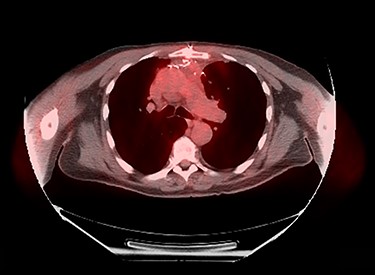

Patient underwent resection of the mediastinal mass. A median sternotomy was performed in typical fashion. Dissection was carried out along the innominate vein where significant desmoplastic reaction from the tumor was present. Upon entry into left chest, the tumor was noted to have contiguous spread into the left upper lobe that unfortunately involved a substantial portion of the phrenic nerve. Decision was made to divide the left phrenic nerve and resect a wedge of left upper lobe en bloc with the tumor. Final pathology report described a 10.2 × 7.5 × 6.0 cm tumor with histology consistent with basaloid carcinoma of thymic gland, with involvement of pulmonary parenchyma and presence of lympho-vascular invasion (Fig. 3). All margins were negative with closest margin being 3 mm. Final pathological stage was pT3N0M0.

Histology of resected thymic gland with enlarged inset showing palisading and squamous features highly suggestive of basaloid carcinoma.